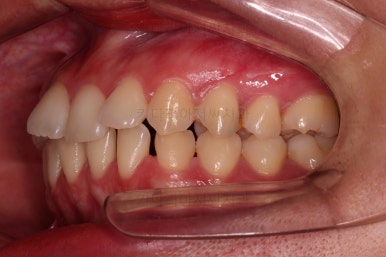

이제 마무리를 해봅니다.

교합 양호하고 치아 사이 틈새도 잘 모아졌습니다.

특히나 틈새가 있었던 환자분의 교정치료는 재발을 할 우려가 크므로 원인 요소가 되는 부분들을 잘 찾고 개선해주며 유지장치도 좀 더 광범위하게 부착해 줍니다.